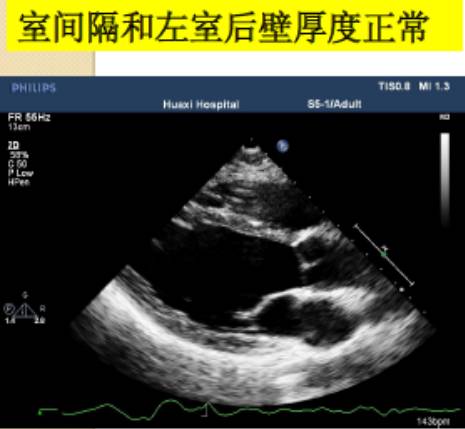

测量位置:胸骨旁左心室长轴,或二尖瓣瓣尖水平左心室短轴切面。

测量内容:室间隔厚度、左心室后壁厚度、左心室内径。

测量时相:收缩末期、舒张末期。

直接二维测量或在二维引导下的M-型曲线上测量。

图|胸骨旁左心长轴切面,二尖瓣瓣尖水平。左图为舒张末期,右图为收缩末期。

随着图像处理技术的改进,已经提高心脏结构的分辨率。可按照真实的组织和血流的界面来测量室间隔和左心室后壁的厚度,而不是像以前测量前缘回声之间的距离。

ASE推荐于二尖瓣瓣尖水平胸骨旁短轴切面直接测量或采用M型曲线测量。M-型超声时间分辨率好。有助于帮助二维超声区分临近左室后壁的肌小梁、室间隔左室面的假腱索、室间隔右室面的调节束等结构。即使采用二维引导也可能无法保证M-型取样线完全垂直于室间隔和左心室后壁。